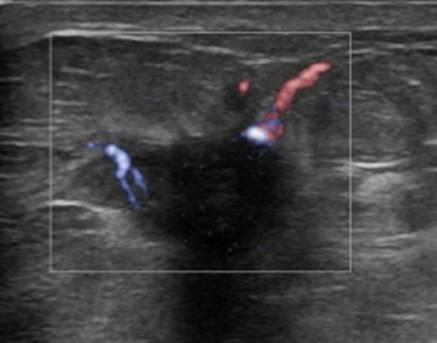

Ung thư vú

Ung thư vú - Ảnh 4

» Thông tin: Nữ giới – 55 tuổi.

» Lâm sàng: Khối tuyến vú.